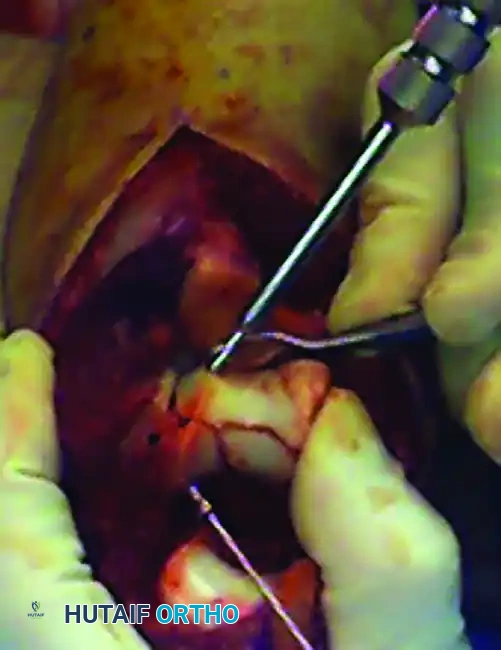

• Use threaded Kirschner wires (K-wires) as joysticks to manipulate the medial and lateral condyles.

• If the articular fracture is simple, reduce the fracture with the joysticks and a Weber clamp, and insert K-wires for provisional fixation.

Provisional fixation

Provisional fixation of the articular block using K-wires and reduction forceps.